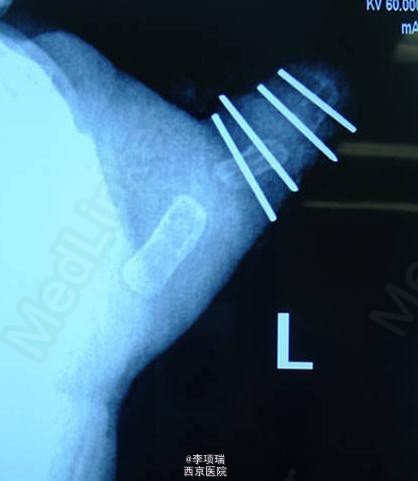

蟹钳指传统BC融合术

患儿,男,1岁2月,蟹钳指,侧弯严重,采用传统BC融合术。术后1个半月,家长述手指已经完全伸直,MP活动可,IP主动活动轻微,被动活动可以正常。